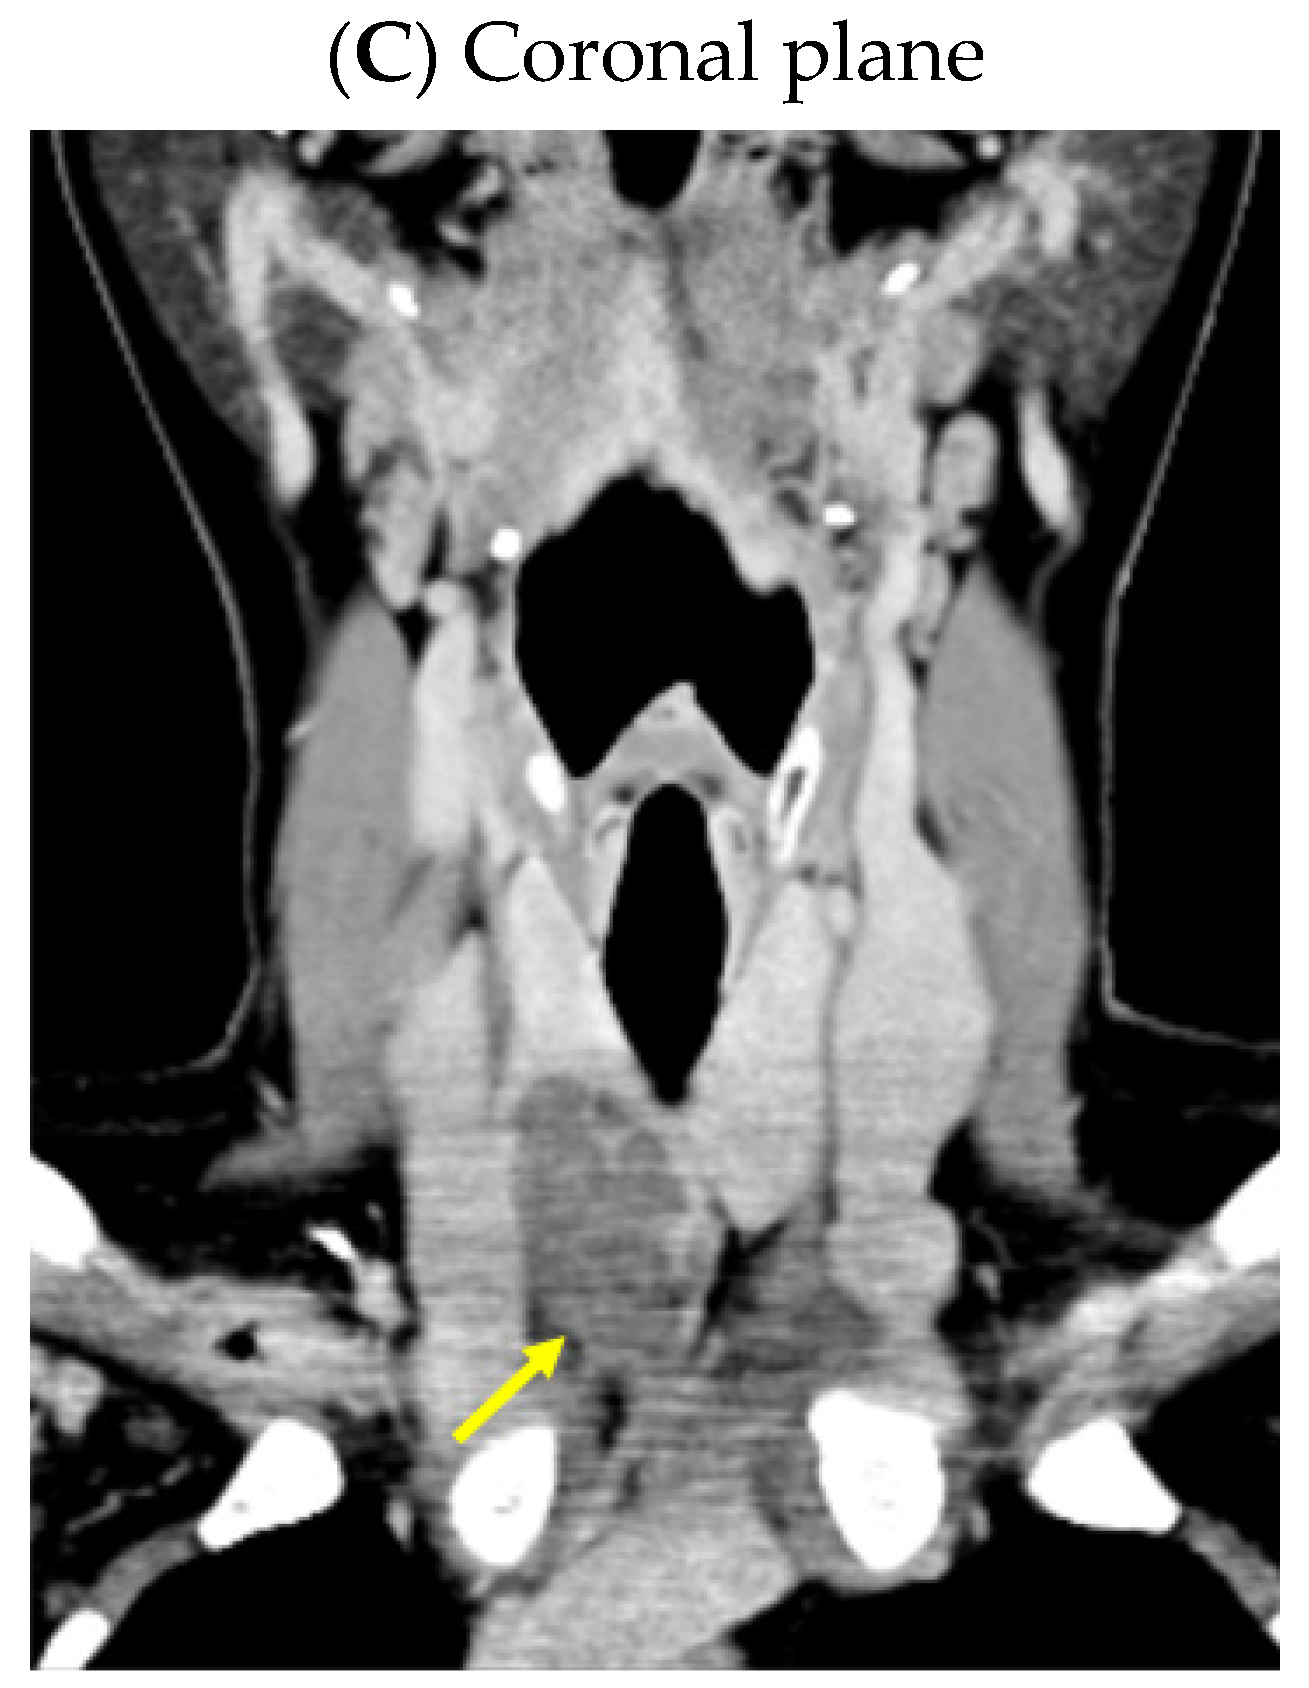

Despite recommendations, she proved poorly compliant once again, and she was re-admitted only seven months later when she suffered a spontaneous fracture at the second cervical vertebra that required immobilization with a cervical collar. Amid this novel hospitalization, the PTH levels remained high with a reduced alkaline phosphatase level (Table 4). A native spine CT revealed an odontoid fracture involving the C1 anterior arch, also confirmed with a native magnetic resonance imaging (MRI) evaluation. Moreover, other left intramaxillary bone lesions were discovered. In this context, the examinations were extended to the level of the skeleton, and the head-thorax-abdomen-pelvis CT scan with intravenous contrast revealed multiple lesions located at different levels, such as the skull (of 3.5 by 3.8 cm), sternum (of 2.9 cm), sacrum (of 4 by 5.5 cm), and pelvis (of 6.5 by 5.5 cm) (Figure 12).

Figure 12.

Brown tumors in an adult lady with poorly controlled renal hyperparathyroidism. (A) Native craniocerebral magnetic resonance imagery (the lesions are highlighted as well as their largest diameter). (B) Intravenous contrast computed tomography showing the mentioned lesions (yellow arrow) at the level of the skull (left) and spine (right).